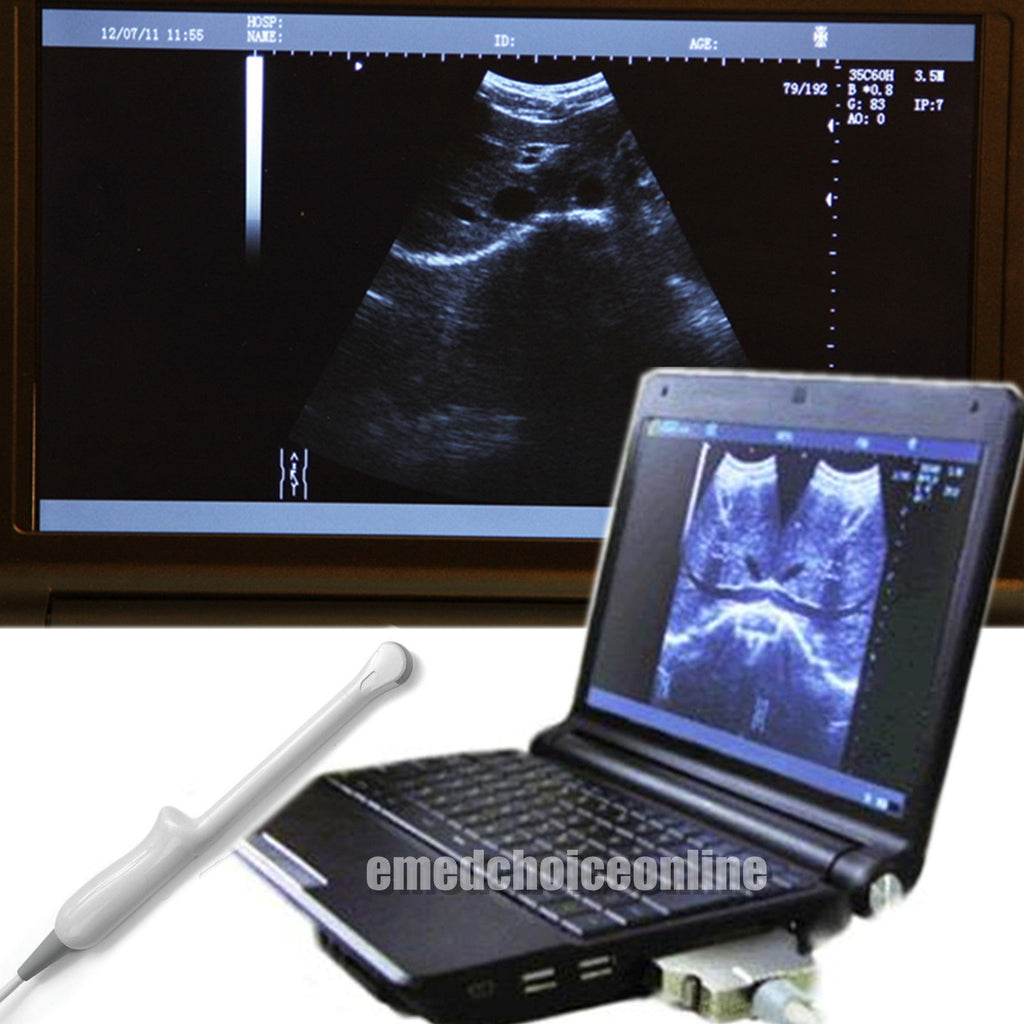

Experience the Precision of a 3D Ultrasound Scanner

A 3D ultrasound scanner is a state-of-the-art imaging device used primarily in obstetrics. It creates detailed three-dimensional images of the fetus, providing healthcare professionals with critical information about the development and wellbeing of both the mother and baby. The 6.5 MHZ transvaginal probe enhances the accuracy of images, making it particularly useful in early pregnancy assessments. With this technology, doctors can visualize the fetus in real-time, leading to better diagnosis and treatment decisions.

Digital laptop 3D ultrasound scanners are portable and user-friendly, allowing healthcare providers to perform examinations in various settings, including clinics and hospitals. The digital format provides higher resolution images compared to traditional scanners, and since it uses advanced software, the analysis is faster and more reliable. This flexibility and efficiency revolutionize workflow, making it easier for medical professionals to access critical data quickly.